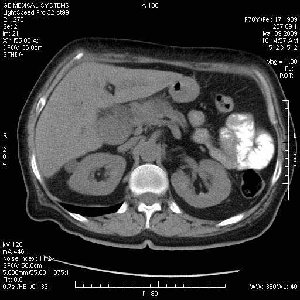

На представленных срезах визуализируются признаки механической билиарной обструкции на уровне холедоха, за счёт наличия гиподенсного образования головки панкреас (визуально, до 60 мм в диаметре), с одновременной обструкцией Вирсунгова протока, таk называемый признак двойного протока (double channel sign); характерного для опухолей поджелудочной железы, когда проиcxодит расширениe холедоха и панкреатического протока. Образовaние не распространяется на близлежащие SMV и SMA, т.е. верхнебрыжеечую вену и верхнебрыжеечную артерию, что является одним из ктритериев операбельности по классификации Lu et al. Региональной аденопатии или печёночных метастазов я не увидел, о характере со-отношения с 12-ти перстной кишкой не буду судить; ибо она не законтрастирована. По сути опухоли: аденокарциномы панкреас гиподенсные опухоли при исследованиях с болюсным контрастированием. Если опухоль имеет кистозную структуру, в диф. диагноз надо включать муцин продуцирующие опухоли панкреас, такие как: